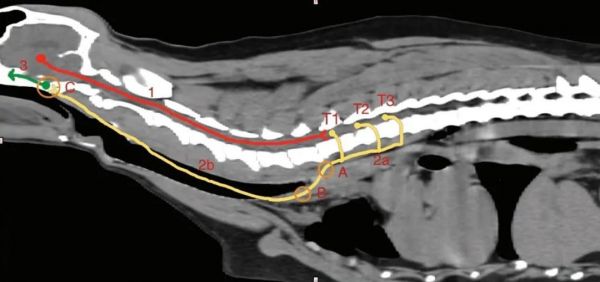

支配眼睛的交感神经通路上任何位置损伤都会出现霍纳氏综合征,可根据病灶在交感神经通路上的位置分为第一节段(中枢)、第二段(节前)、第三节段(节后)[1]。

图中红色表示中枢节段。绿色表示节后节段。黄色是节前节段 [5]。

第一节段(中枢)神经元起源于下丘脑 [6],经过脑干,沿着颈段脊髓从第二胸椎进入胸腔。脑干或颈段脊髓的上运动神经元病灶较少引起霍纳氏综合征,但如继发于创伤、梗死、肿瘤或炎症性疾病时则可能出现。如果是中枢性病变,霍纳氏综合征不太可能是唯一的临床症状。总是伴有其他的神经功能异常症状,如共济失调、瘫痪 / 抽搐、姿势反应缺损 (脑干或脊髓病变)、精神状态改变和其他颅神经受累 ( 脑干病变)。

第二节段(节前)神经元从第 1-3 胸椎脊髓节腹侧神经根内离开脊髓,而后由脊神经形成胸段交感干,并在胸腔内向头侧延伸与胸交感干会和 [6]。在颈部,交感经轴突行走在迷走交感干内向头侧延伸,到达鼓泡附近,直到与颅颈神经节发生突触 [6]。第二节段神经元损伤可发生于颈膨大处 (C6-T2) 的脊髓损伤,常继发于创伤、梗死、肿瘤或炎症性疾病 [1]。受波及的动物会表现出受波及前肢的下运动神经元(lower motor neuron, LMN) 症状,同侧后肢的上运动神经元 (upper motor neuron, UMN) 症状,及霍纳氏综合征 [1]。

第三节段(节后)的交感神经支配路径为向后通过中耳鼓室枕骨裂 [6],进入中耳,并与舌咽 (CN9) 一同进入颅腔,在眼眶裂处离开颅腔并分布于眼眶周围平滑肌、上下眼脸、第三眼脸和虹膜肌肉。第三节段霍纳氏综合征常见于外伤、感染 / 炎症、肿瘤和特发性 [7]。